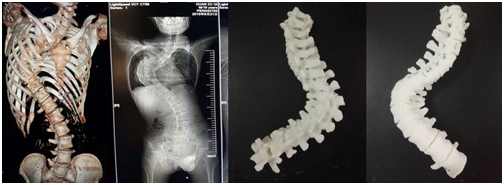

会上,SICOT中国部数字骨科学会主任委员裴国献教授对数字骨科现状、存在问题及未来对策进行了淋漓尽致的分析,并对我省的数字骨科发展和3D打印技术的应用表示赞许。会议对临床医学院/附属医院骨三科朱述浪主任团队在九江地区率先利用3D打印技术为脊柱侧弯患者制作脊柱模型给予高度肯定。该次手术中,术前直观、准确地掌握脊柱畸形的具体病变情况,制定手术计划,术中与模型对照.判断畸形椎体椎弓根的位置和方向;患者手术过程顺利,矫形和内固定满意,未出现神经、血管损伤等并发症。

利用3D打印技术给脊柱侧弯患者制作的模型

对于一些复杂骨折和畸形,单纯凭借CT或MRI等影像学资料难以对局部解剖结构形成形象、直观的认识,手术难度和风险较大。3D打印骨骼模型将真实的骨骼结构呈现在眼前,可以更加直观地了解病变的严重程度,分析导致病变的原因和机制,有助于疾病的分型及诊断,同时还可用来计划和模拟手术。这是3D打印技术在骨科领域应用研究的重点内容之一,国内外已经有较多学者在这方面做了大量研究工作。